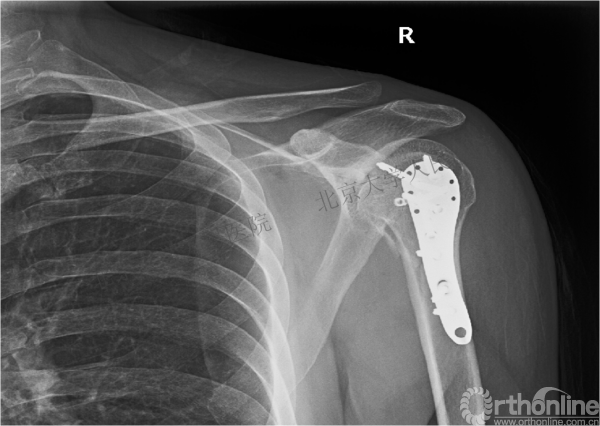

X线检查

1.右肱骨近端骨折

2.右肩关节后脱位

术后影像学检查